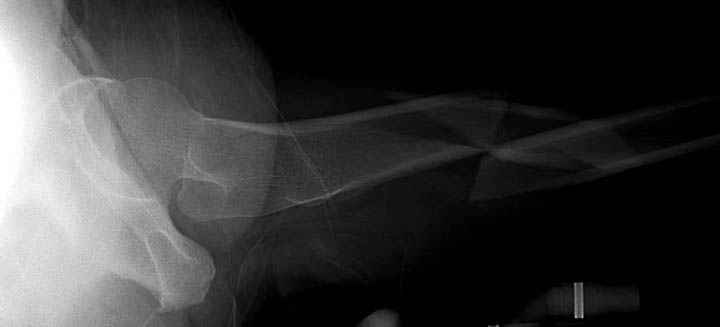

При поступлении бедро напряженное, сосудистых и неврологических расстройств нет. На рентгенограмме оскольчатый перелом бедра с вовлечением проксимальной спирали в шейку бедра.

Имя     : 3 Femur lat.jpg

Тип     : image/jpeg

Размер  : 18088 байтов

Url     : http://weborto.net:8080/pipermail/ortho/attachments/20090531/91bb3dda/attachment-0005.jpg